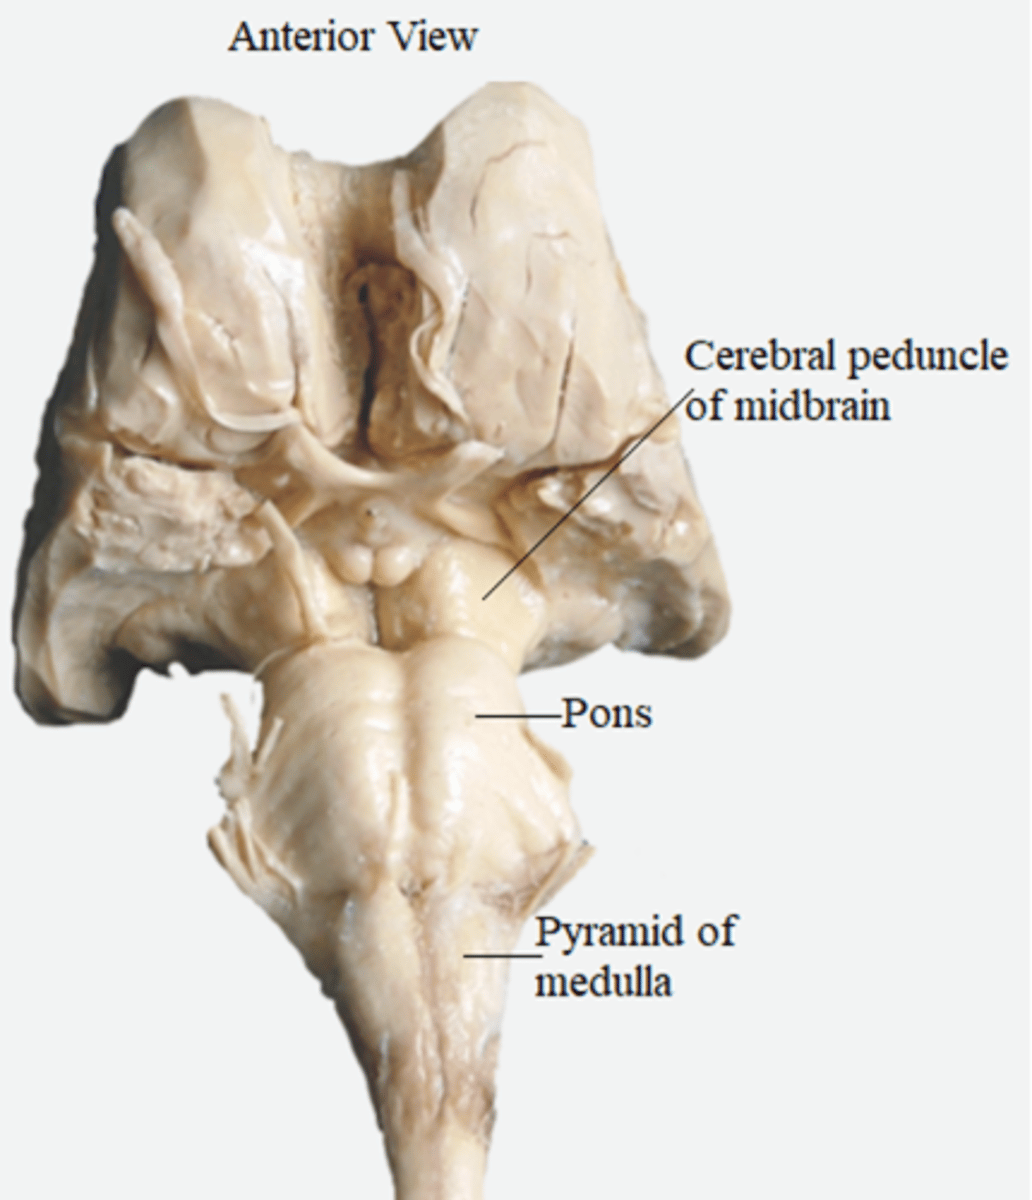

what are the 3 parts of the brainstem?

1. midbrain

2. pons

3. medulla

which region of the brainstem contains the cerebral penduncles? what is the ventral portion of the cerebral peduncles that contain corticospinal and corticobulbar fibers?

midbrain; crus cerebri

what medulla structure is a swelling along the ventral surface composed of motor fibers of corticospinal and corticobulbar tracts?

pyramid